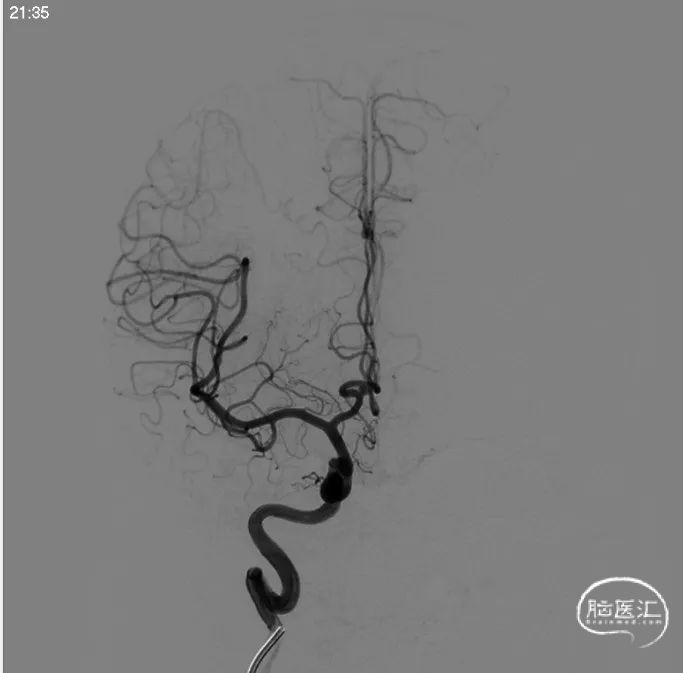

术前左侧侧位

术前左侧正位

术前右侧正位

术前右侧侧位

术前工作位

左侧3D

右侧3D

取右侧股动脉为穿刺点,Seldinger法穿刺成功后置入6F鞘。行全脑血管造影显示左侧颈内动脉眼动脉段动脉瘤,约10*7mm大小,瘤颈6.1mm。6F 90长鞘+115cm 6F SKATHI中间导管超选至左侧颈内动脉海绵窦段。